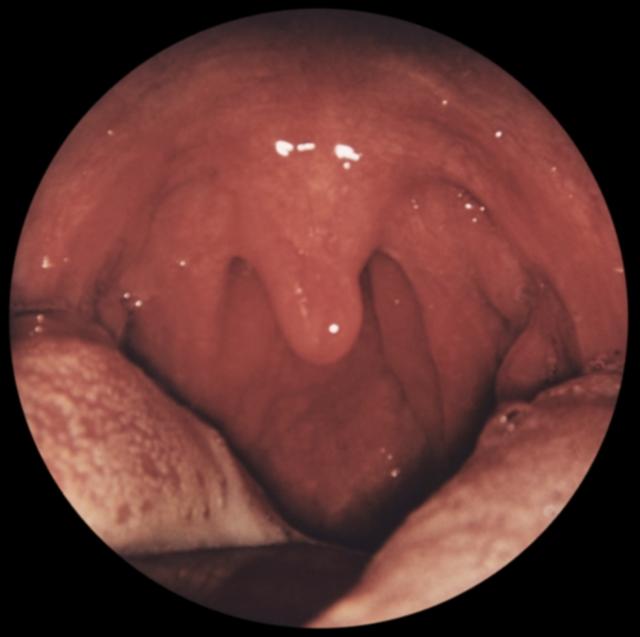

Рис. г). Вид зева при хроническом боковом фарингите.